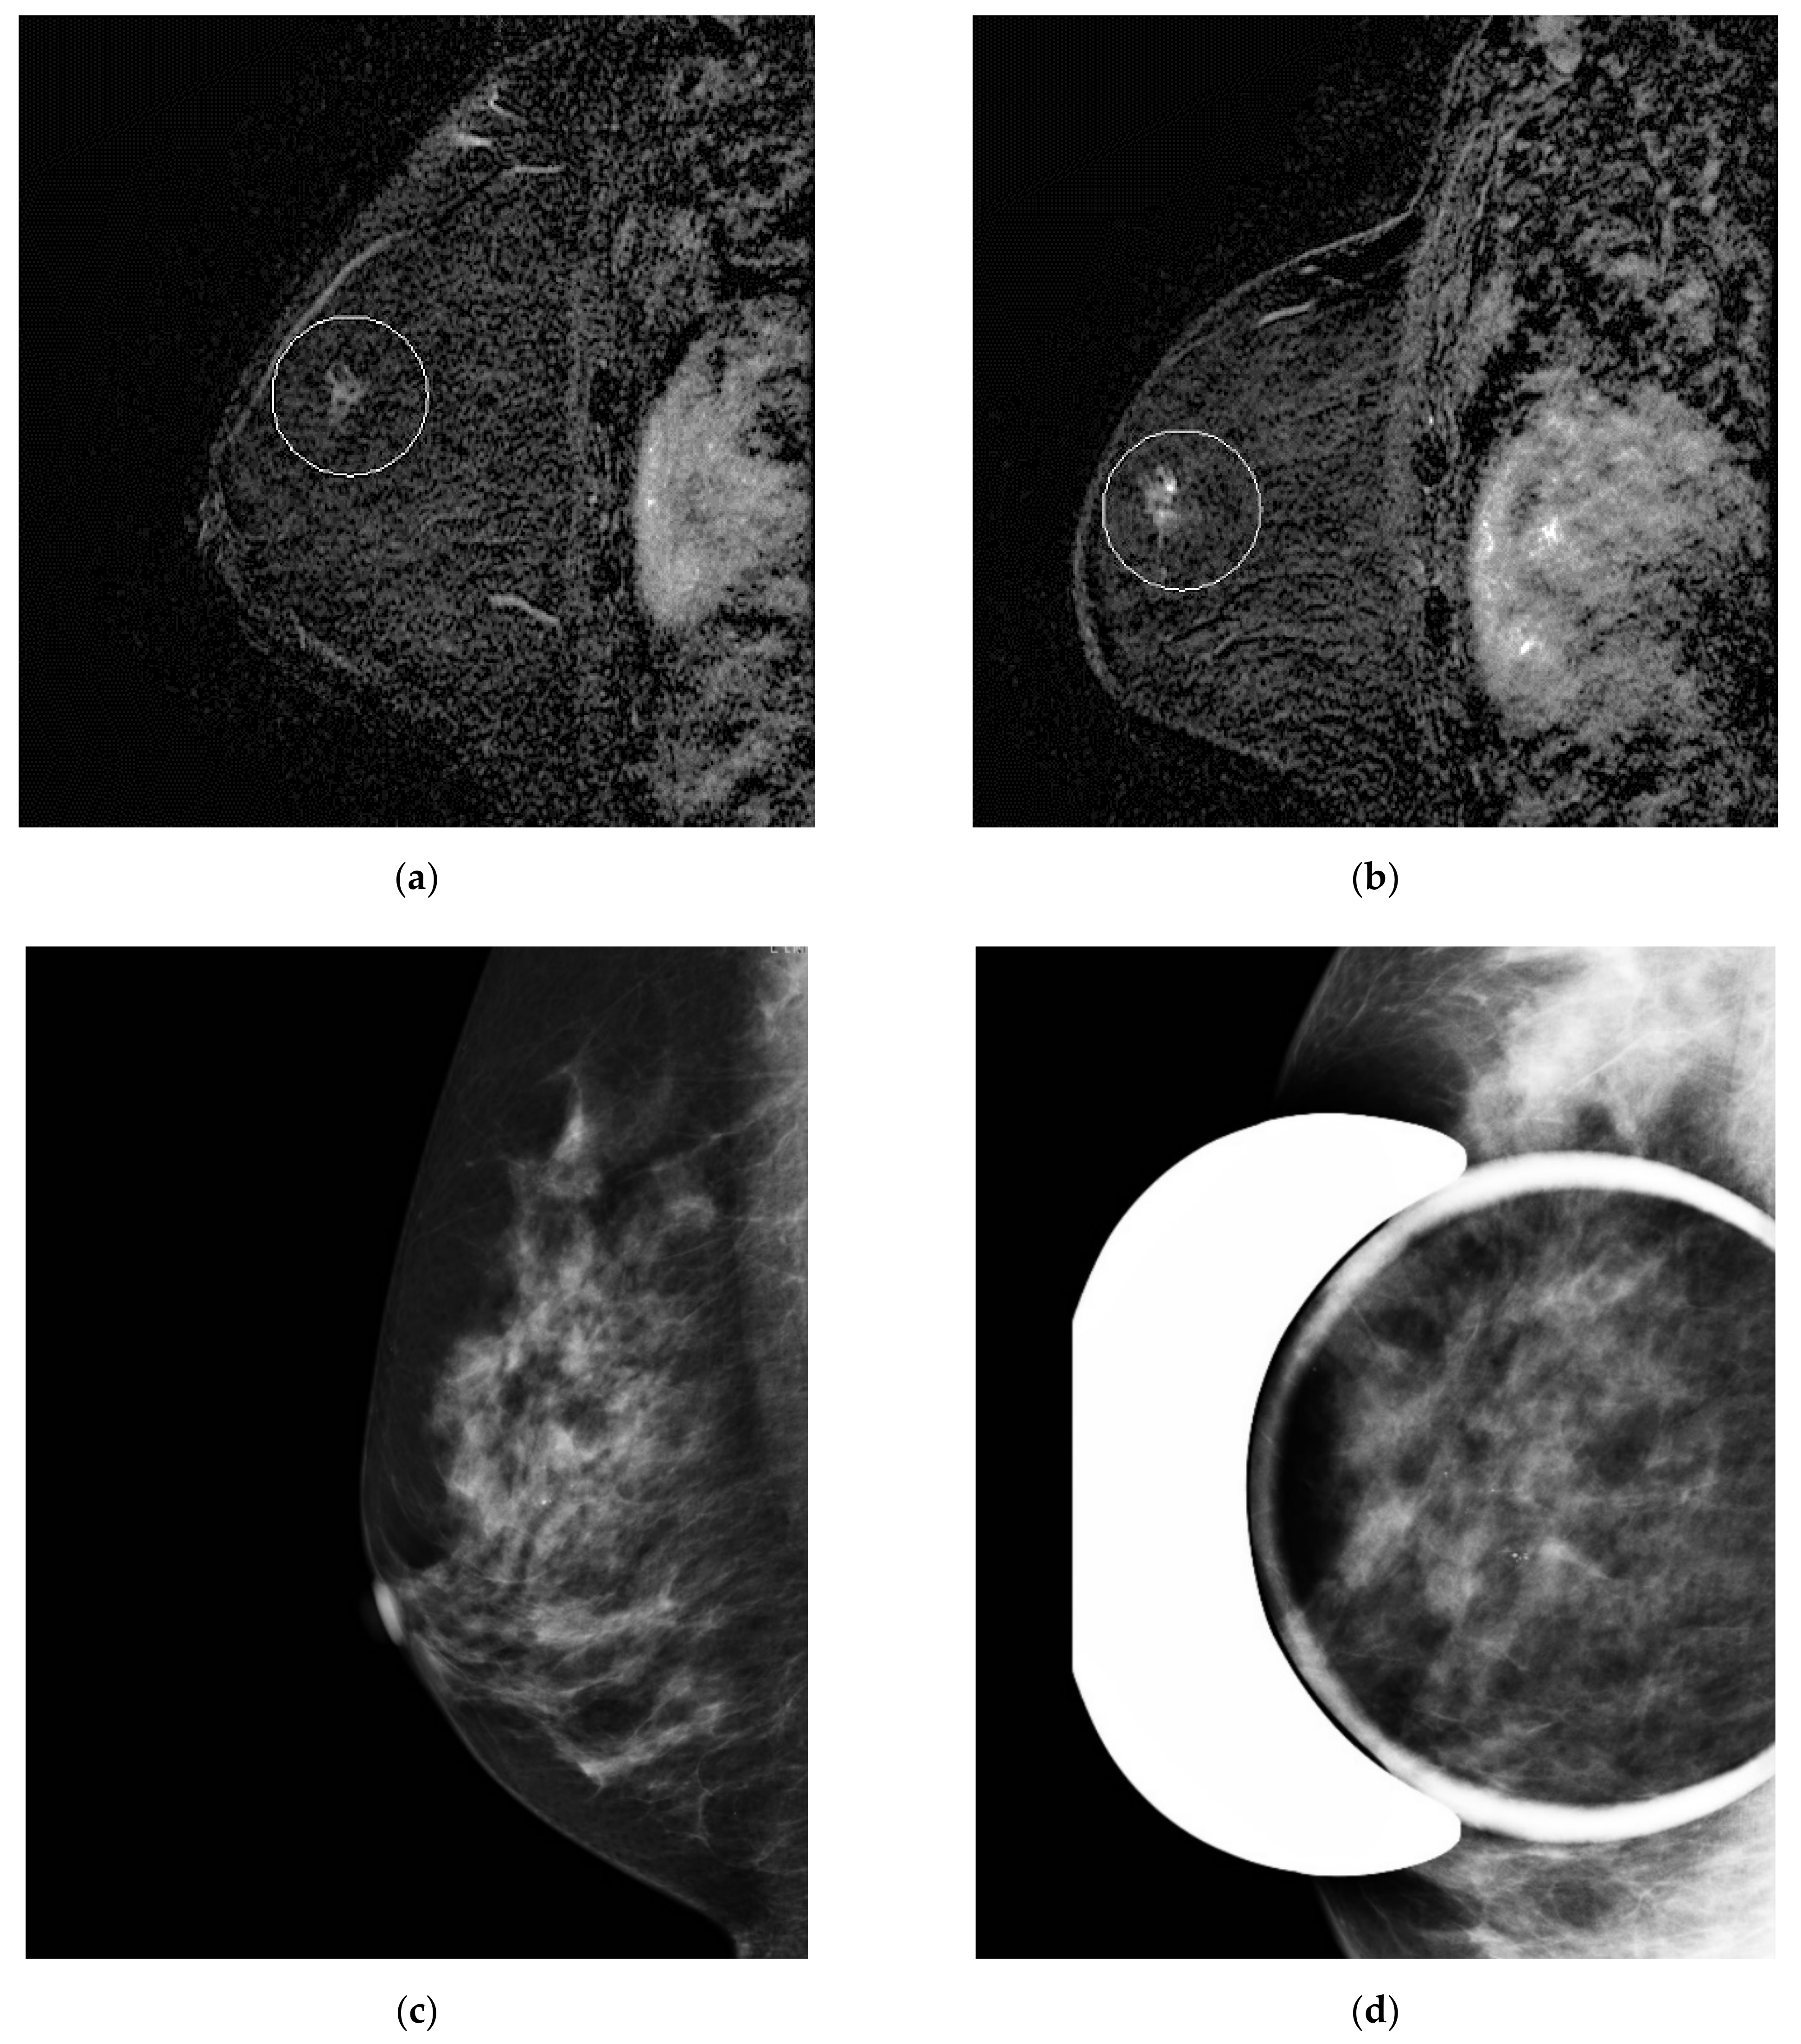

Figure 3. Misinterpreted stable non-mass enhancement between (a) MR A and (b) MR B. Calcifications were visualized in the same location and increasing in number on (c) the concomitant mammogram and (d) magnification views.